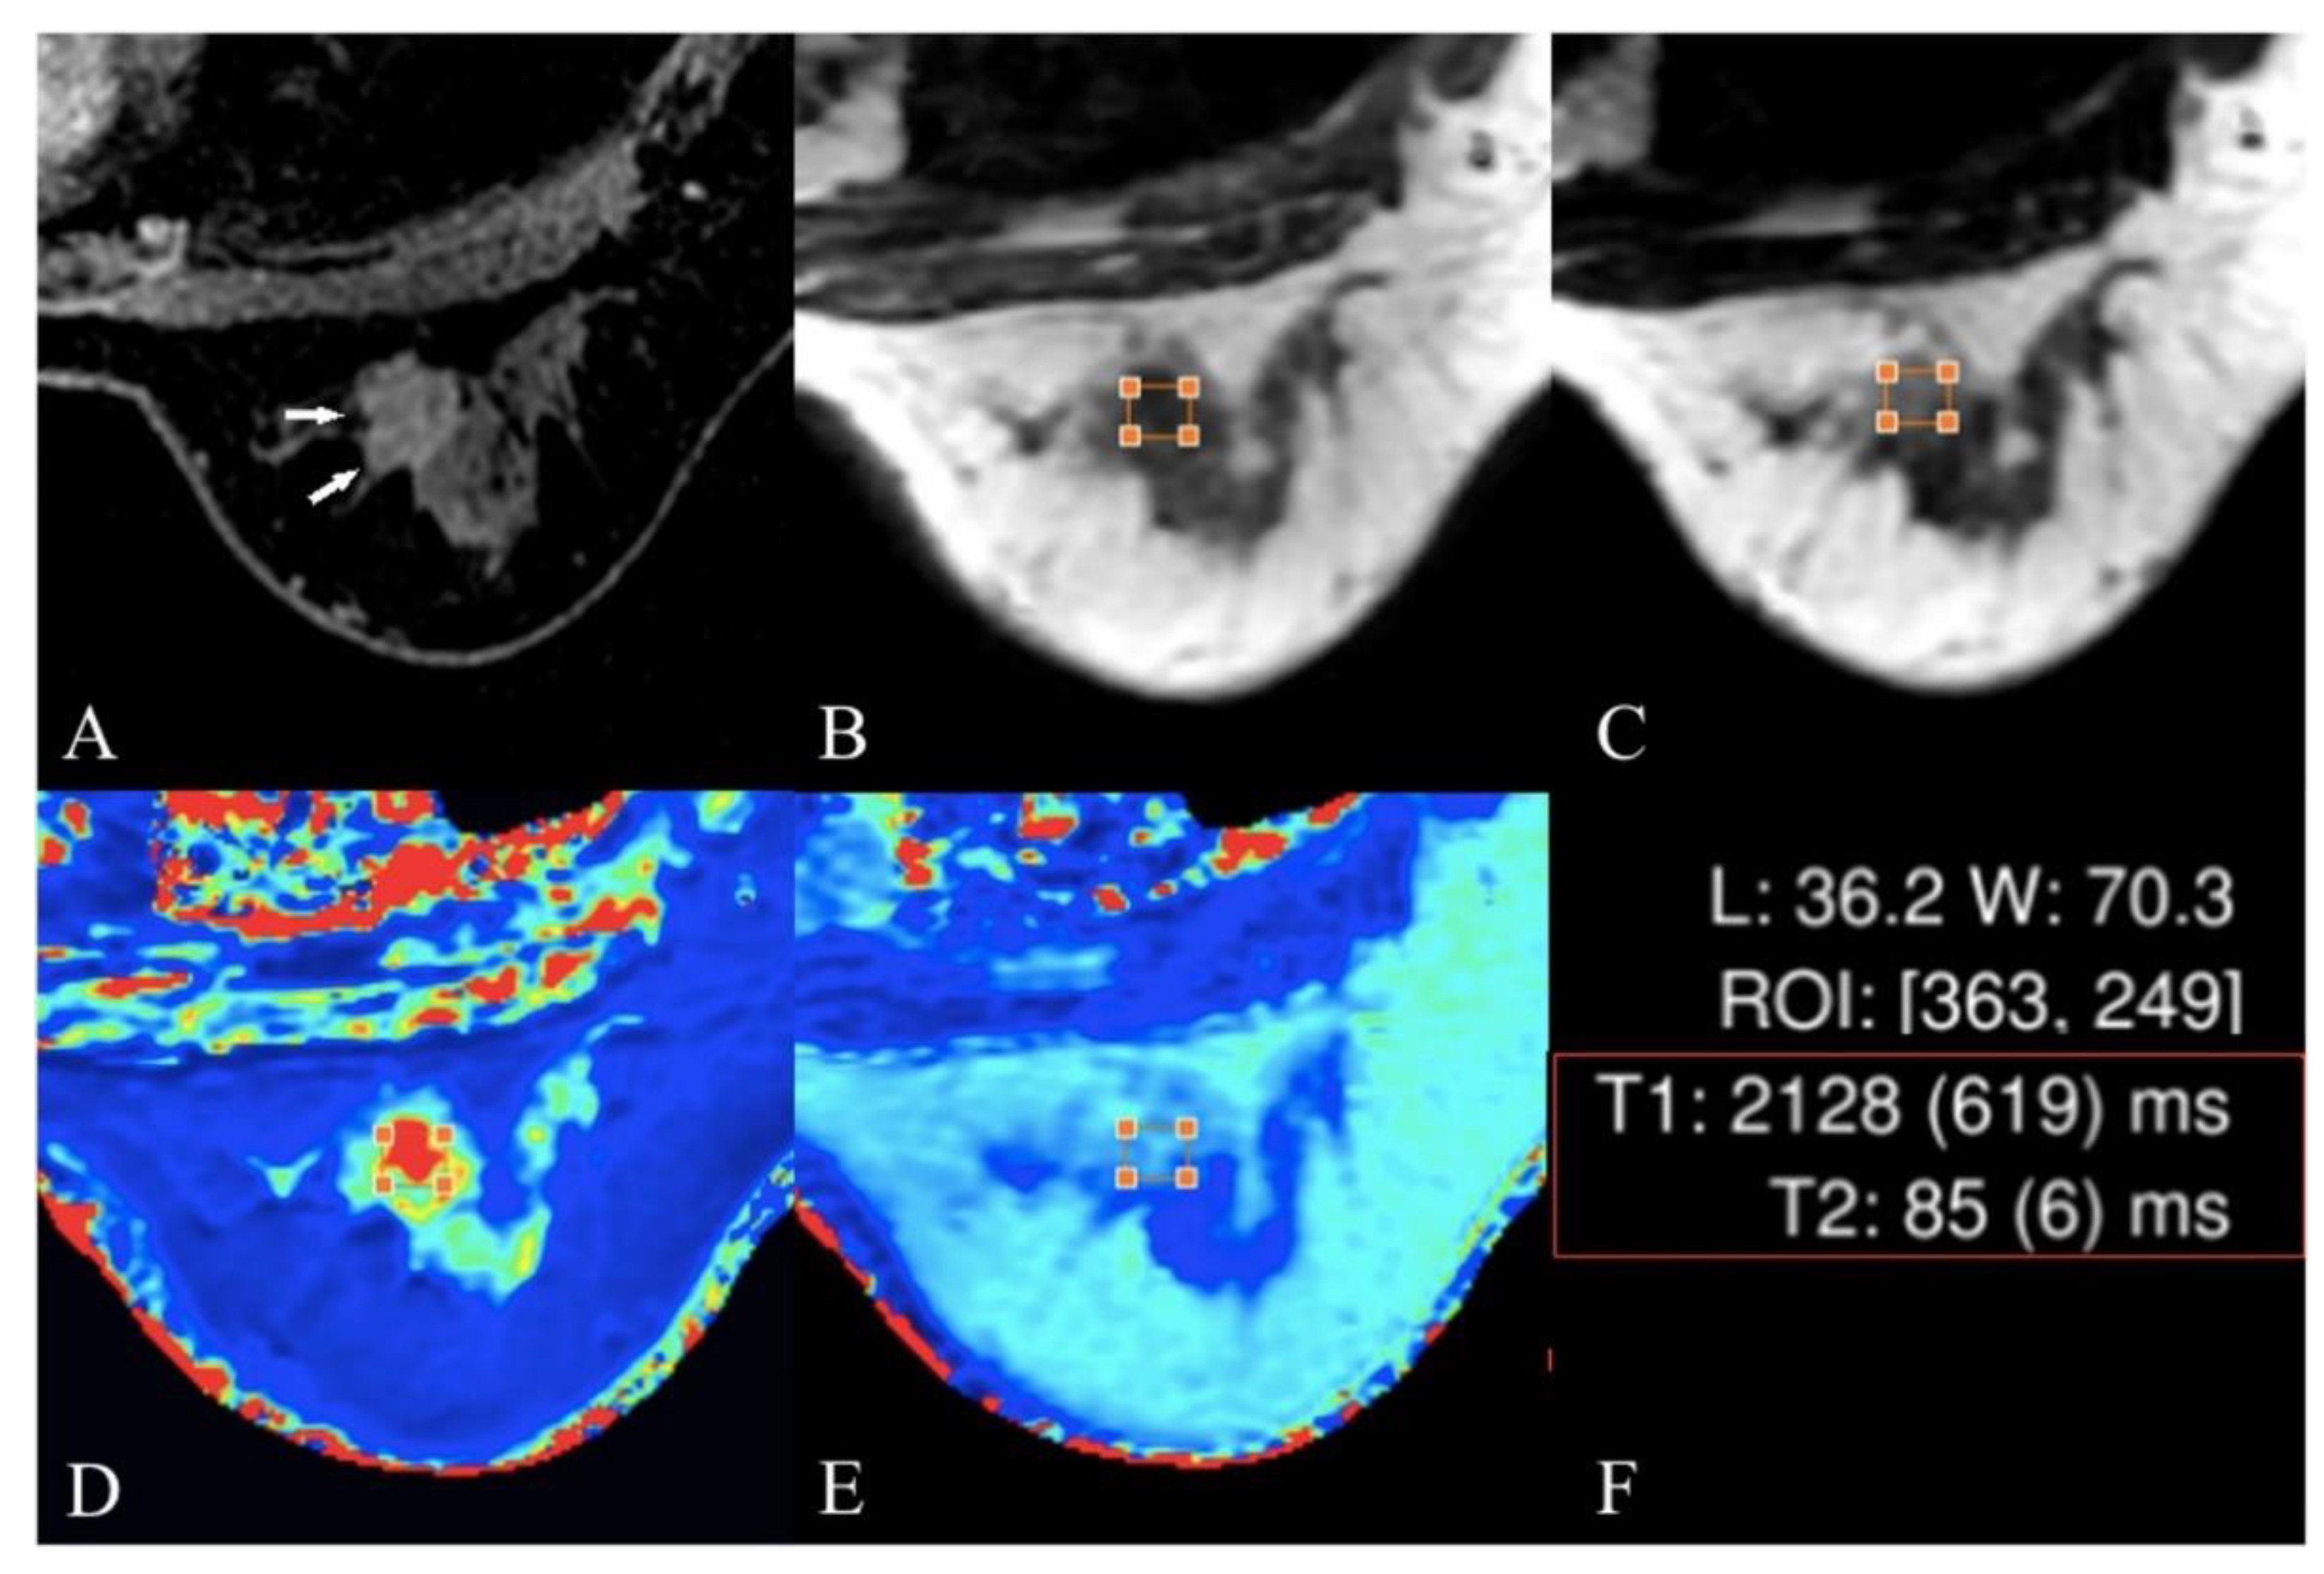

4.5. T2 and T2* Mapping

- Liu, L.; Yin, B.; Geng, D.Y.; Lu, Y.P.; Peng, W.J. Changes of T2 relaxation time from neoadjuvant chemotherapy in breast cancer lesions. Iranian Journal of Radiology 2016, 13. [Google Scholar] [CrossRef]

- Seo, M.; Ryu, J.K.; Jahng, G.-H.; Sohn, Y.-M.; Rhee, S.J.; Oh, J.-H.; Won, K.-Y. Estimation of T2* relaxation time of breast cancer: correlation with clinical, imaging and pathological features. Korean journal of radiology 2017, 18, 238–248. [Google Scholar] [CrossRef]

- Liu, L.; Yin, B.; Shek, K.; Geng, D.; Lu, Y.; Wen, J.; Kuai, X.; Peng, W. Role of quantitative analysis of T2 relaxation time in differentiating benign from malignant breast lesions. Journal of International Medical Research 2018, 46, 1928–1935. [Google Scholar] [CrossRef]

- Meng, T.; He, N.; He, H.; Liu, K.; Ke, L.; Liu, H.; Zhong, L.; Huang, C.; Yang, A.; Zhou, C. The diagnostic performance of quantitative mapping in breast cancer patients: a preliminary study using synthetic MRI. Cancer Imaging 2020, 20, 1–9. [Google Scholar] [CrossRef] [PubMed]